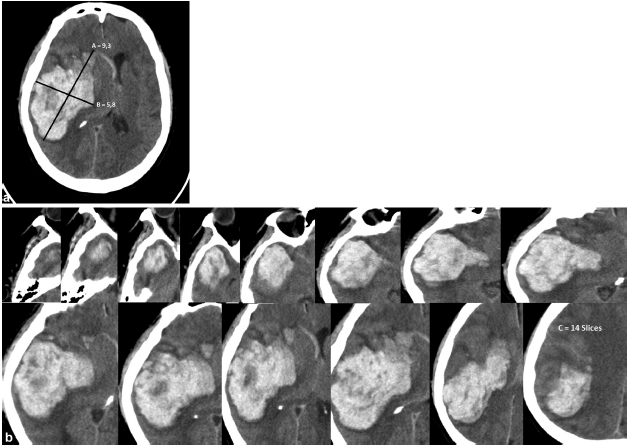

La medición del volumen de un hematoma intraparenquimatoso se realiza mediante un método denominado ABC/2 que está basado en el cálculo de volumen de un elipsoide o esfera.2,4,5,6,7

Fue reportado por primera vez por Kwak.8

Para llevar a la práctica este método de medición del volumen de los hematomas intraparenquimatosos mediante una TC de cerebro, se elige el corte con el área de mayor sangrado, midiéndose el máximo diámetro anteroposterior del mismo (parámetro A). El parámetro B corresponde al diámetro transversal de la lesión en ese mismo corte.3,4,7 El parámetro C es el número de cortes en los que se aprecia sangrado multiplicado por el espesor de corte (►Fig. 1).1,3,4,7

La fórmula es: A x B x C /2 y el resultado final se expresa en centímetros cúbicos.1

Estudios de cohorte recomiendan el tratamiento quirúrgico en los pacientes con un volumen de sangrado mayor a 25 cm3; en los casos de lesiones de menor volumen la indicación es variable, dependiendo del estado clínico del paciente.4

El método ABC/2 permite cuantificar rápidamente el volumen de un hematoma sin necesidad de software especializado, pudiendo ser realizado con el paciente en la sala de urgencias. Sin embargo, algunos autores consideran el método poco específico, ya que puede subvalorar el volumen del hematoma, especialmente en aquellos sangrados de bordes irregulares, con contornos polilobulados o que no tienen forma elíptica, pudiendo considerarse otras técnicas de volumetría (planimetría) asistida por computadoras que incorporan un software especial.1,3,4,5,6,7